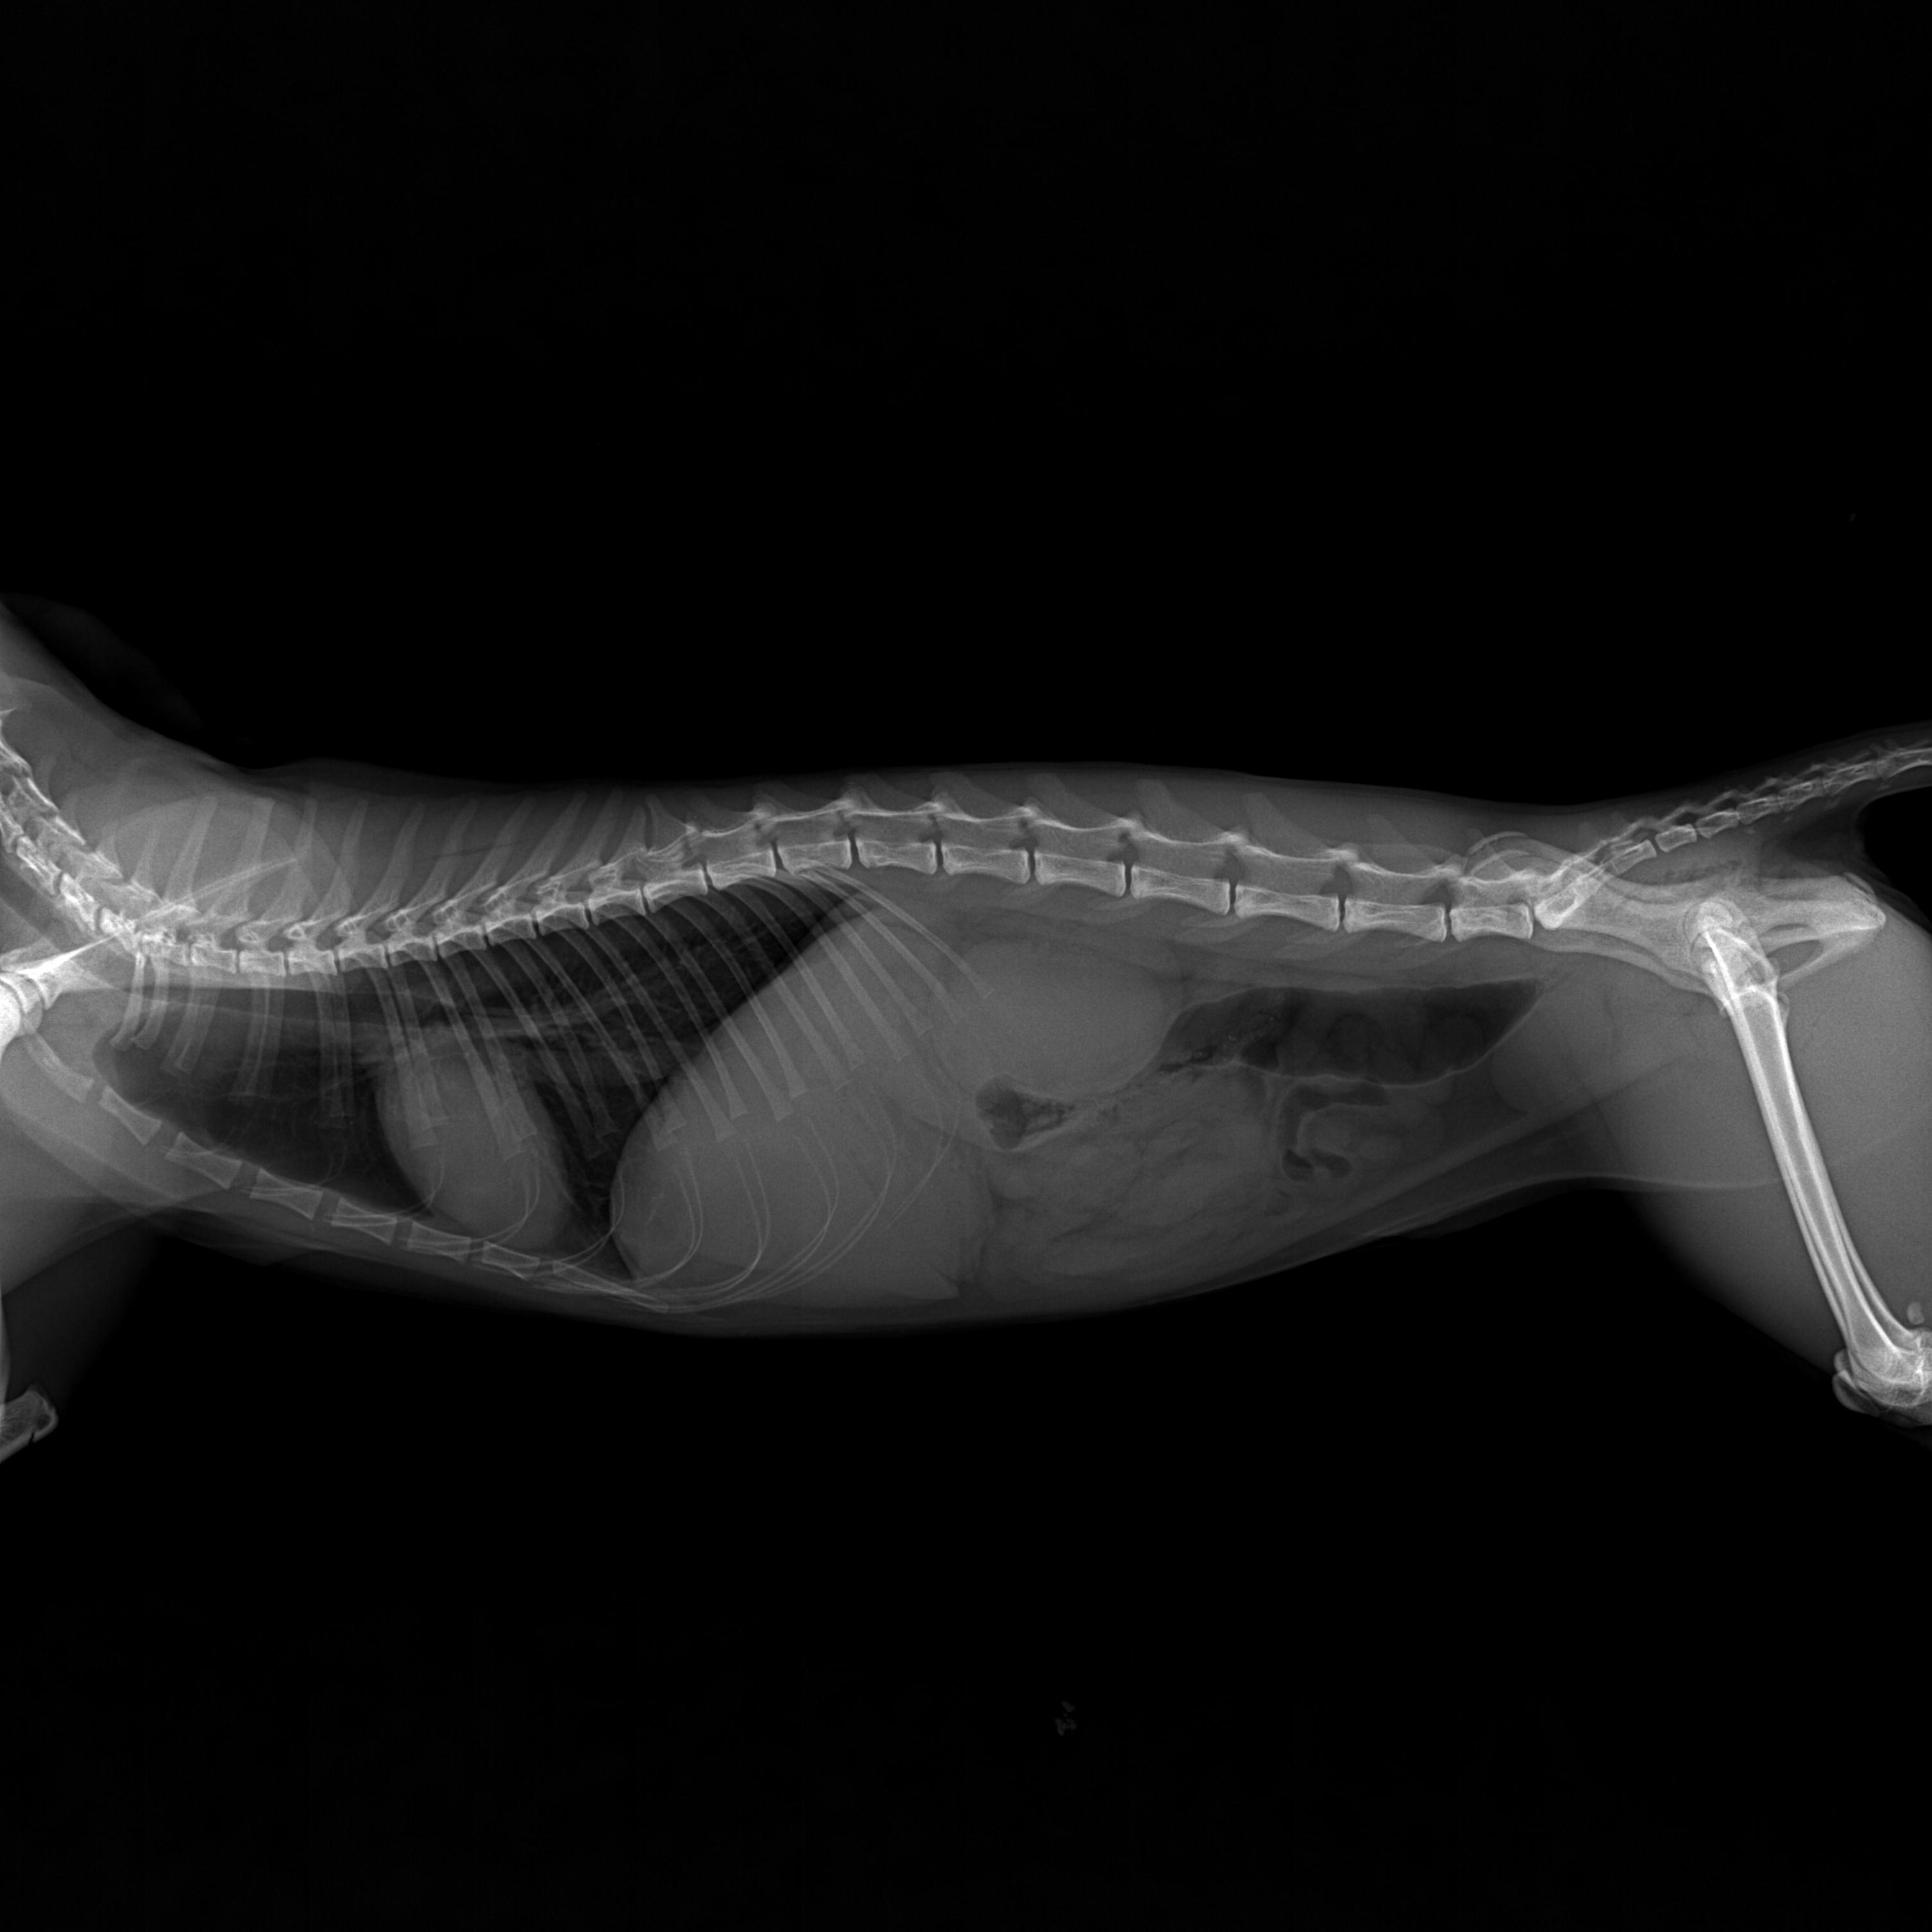

| 치료과정 | 2024년 12월 7일 토요일 오전에 피침을 흘리며 기력 없이 쓰러져 있던 동경이는 바로 병원으로 이동했습니다.. 12월 초부터 이상 징후가 있었던 동경이를 지켜보면서 혹시나 범백이 아닐까 의심스러웠던지라 의사 선생님께 그동안의 상황을 설명하고 범백키트 검사를 먼저 하였습니다.. 너무나도 다행스럽게 범백은 음성으로 나왔습니다 그동안 만약 범백이라면 밥자리에 있는 많은 아이들은 어쩌나 싶어서 정말 걱정이 되었거든요 너무 너무 다행스런 순간이었습니다.. 이후 엑스레이와 혈액검사를 진행 하였고 엑스레이 결과 위장 내용물이 한개도 없었다는..ㅠ ㅠ 그동안 전혀 먹지를 못했다는 것이었지요 얼마나 아프고 힘들었을지 .. 동경이 한테 너무 미안 했습니다 며칠이라도 빨리 병원에 데리고 왔으면 덜 고생 했을텐데.. 미안하고 또 미안 했어요 .. 모든 검사결과 신장이 거의 두배로 부어있었고 혈액검사도 신장수치와 췌장수치를 포함한 모든 수치가 많이 높게 나왔습니다 선생님께서 급성신부전으로 진단하시고 바로 수액처치와 필요한 치료에 들어갔습니다.. 입원 이틀동안은 자발식이가 전혀 없어서 걱정스러웠는데 삼일째 드디어 동경이가 먹기 시작했습니다.. 입원 삼일째부터 동경이는 그동안 굶은것을 만회 하는것처럼 너무 너무 잘 먹어주었습니다 매일 매일하는 링거치료도 잘 견뎌주고 착한 아이라고 선생님께 칭찬도 많이 받았어요..ㅎㅎ 저를 보면 반가움의 인사가 비록 하악질로 시작 됐지만 잘 이겨내고 서서히 회복해가는 동경이를 얼마나 기쁘고 감사하던지 .. 의사 선생님께서 입원 치료중 중간 시점에 혈액검사를 권하였지만 검사 자체가 동경이 한테 큰 스트레스가 될수 있으니 며칠 더 치료후 검사를 해달라고 했고 드디어 12월 17일 혈액검사를 했습니다.. 피 뽑고 결과를 기다리는데 어찌나 떨리던지 ..ㅠ 검사 결과 동경이의 신장을 포함한 모든 수치가 정상으로 나왔고 퇴원이 가능해졌습니다 |